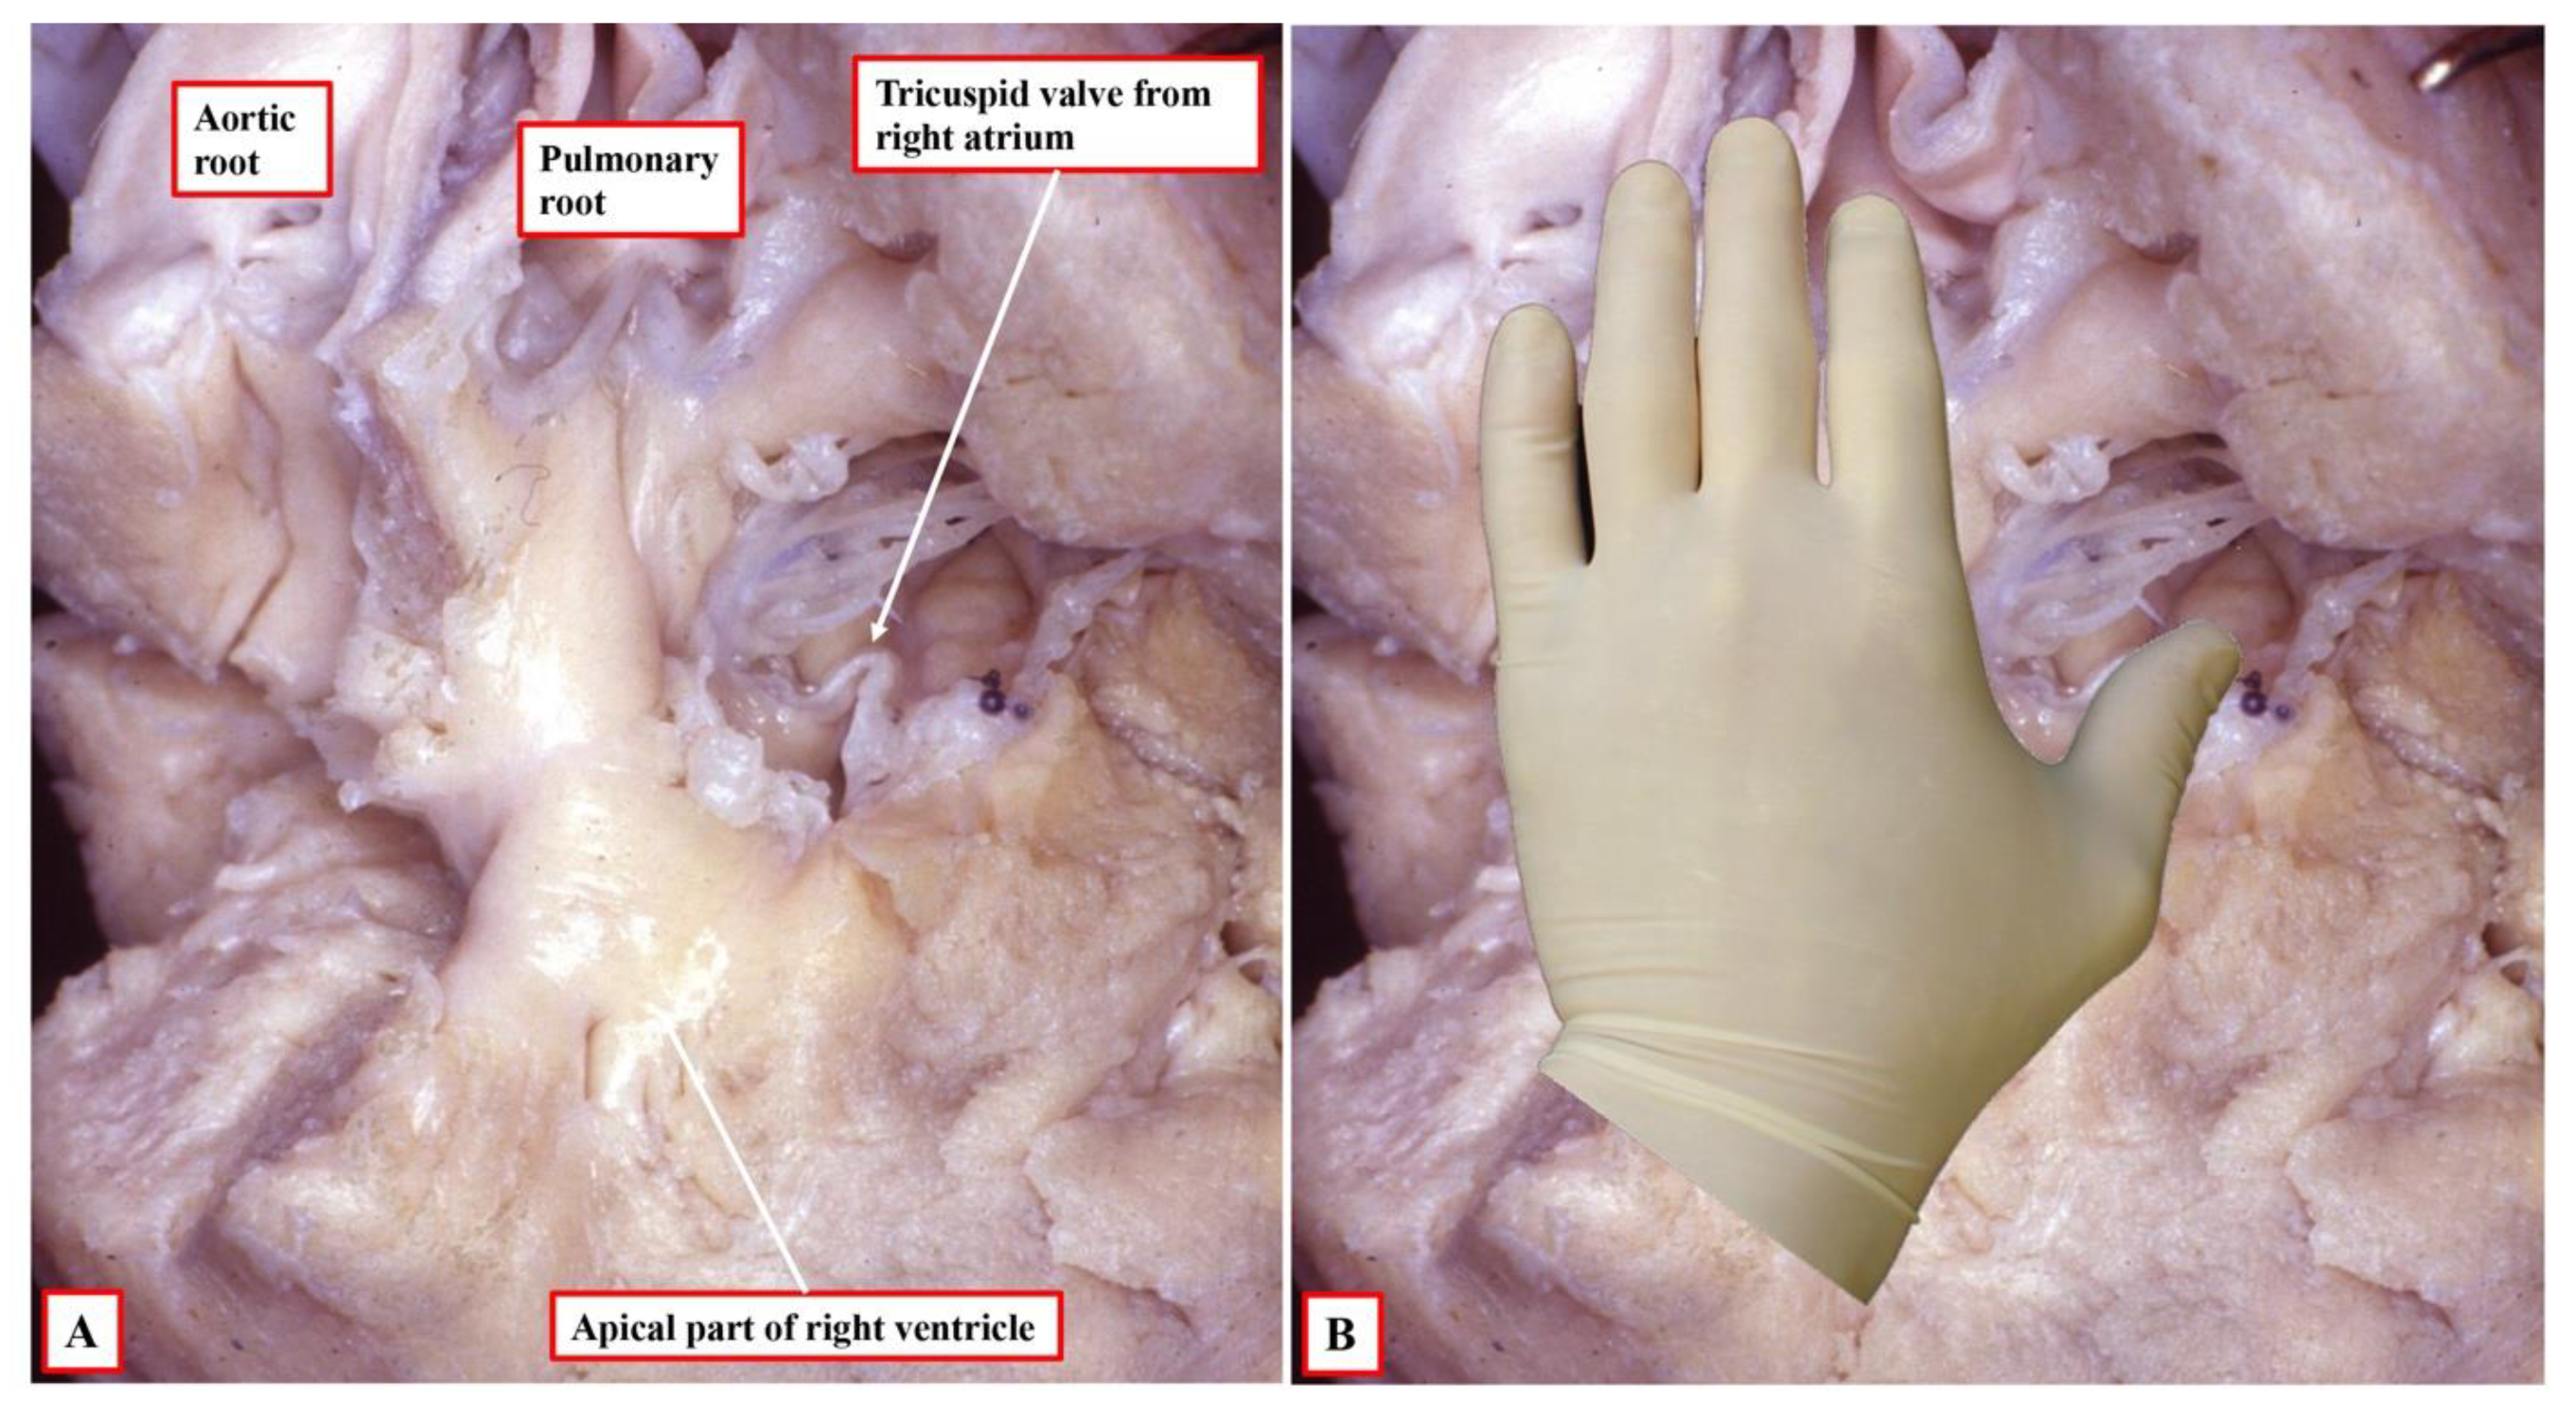

Figure 2A).

The arrangement at the early stage is pertinent to the commonest variant of tricuspid atresia, which is shown in

Figure 1. Since the right side of the atrioventricular orifice opens into the developing left ventricle, the developing right ventricle lacks a direct atrial input (

Figure 2B). In consequence, the developing right ventricle, at this early stage, is incomplete, possessing only apical and outlet components. The left ventricle, in turn, possesses only inlet and apical components. At this early stage, therefore, it is not possible to determine with precision the topological arrangement of the ventricle mass. The relationship of the incomplete right ventricle to the dominant left ventricle could be changed simply by rotating the heart itself.

Figure 2B).

At the initial stage, however, as also explained, the developing right ventricle lacks its inlet component. It is not possible, therefore, to establish its topology with certainty since it is not possible to anchor the thumb. This remains a problem when seeking to establish topology in postnatal hearts with univentricular atrioventricular connection to a dominant left ventricle, such as double inlet left ventricle or the commonest variant of tricuspid atresia. In most instances, nonetheless, it is possible to infer the likely ventricular topology according to the location of the incomplete ventricle. Almost without exception in these settings, the incomplete right ventricle is carried on the shoulder of the dominant left ventricle. When there is usual atrial arrangement, therefore, a right-sided and anterior location of the incomplete right ventricle can be taken as evidence of right-handed topology, for example, in the heart with tricuspid atresia, as shown in

Figure 1A.